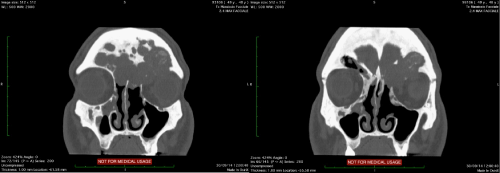

4. Eight months after the symptoms recurred so the patient underwent diagnostic nasal endoscopy that showed a large area of fibrosis at the region of the left frontal-nasal duct. A CT scan showed bilateral recurrence of mucocele within a mega-frontal-sinus. The lesion reached the left supraorbital region with erosion of the roof of the ipsilateral orbit (Figure 1).

Figure 1 CT scan coronal view. The lesion reached the left supraorbital region with erosion of the roof of the ipsilateral orbit.

The TC postoperative control, performed after 24hours from surgery revealed no intracranial complications but the correct fat positioning in the frontal sinus.